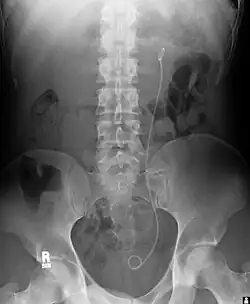

- ureterale, suprapubische oder urethrale Katheterisierung, z. B. Doppel-J-Katheter (Ureterstent, pigtail-Katheter)

Der Harnstau lässt sich sonografisch in vier Schweregrade unterteilen:

Harnstau Grad I: Entspricht einer Dilatation nur des Nierenbeckens. Zur Verlaufsbeurteilung empfiehlt sich die Ausmessung der echofreien Ausdehnung in Nierenlängsachse. Differenzialdiagnostisch muss an ein ampulläres Nierenbecken gedacht werden.

Harnstau Grad II: Hier findet sich eine Dilatation sowohl von Pyelon als auch von Nierenkelchen – das Parenchym ist noch normal. Zur Verlaufsbeurteilung sollten Kelch- und Pyelonweiten ausgemessen werden.

Harnstau Grad III: Zur zweitgradigen Stauung kommt noch eine beginnende Parenchymverschmälerung hinzu.

Harnstau Grad IV: Die Maximalvariante des Harnstaus zeigt sich in einem kompletten Verlust des Nierenparenchyms – die hydronephrotische Sackniere.